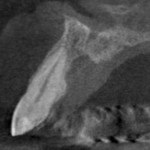

The lateral images taken with the Kodak 9000 CBCT showed a different story however. All the 0.076 mm sections showed a normal periodontal ligament space surrounding tooth #11 (and tooth #21). There was however a slightly enlarged incisive canal situated palatally, directly behind the root of tooth #11. The two-dimensional image overlayed the root on the incisive canal and gave the appearance of a periapical radiolucency usually seen with chronic apical periodontitis.

CBCT #2